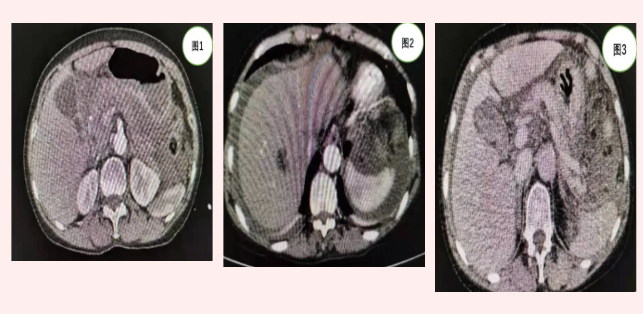

患者張某入院時,急診行全腹CT(見圖1)等相關(guān)檢查發(fā)現(xiàn)上腹部包塊但未見明顯肝脾破裂及腹腔積液。由于患者外傷,病情隨時可能加重,主管醫(yī)師張浩杰嚴密觀察病情時,患者腹痛加重,血紅蛋白進行性下降,立即復(fù)查上腹部增強CT(見圖2、3)發(fā)現(xiàn)腹腔大量積液。